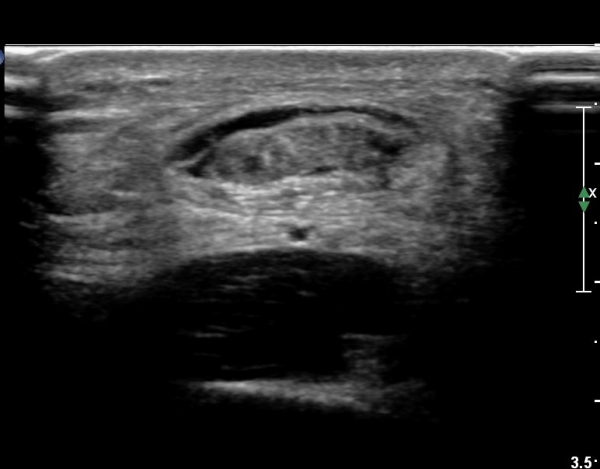

¾ÆÅ³·¹½º°Ç Ⱦ´Ü¸é°Ë»ç¿¡¼ ¾ÆÅ³·¹½º°Ç Àú¿¡ÄÚ ºÎÁ¾, ¿¬°á¼º ¼Ò½Ç, °ÇÁÖÀ§ ¼ö¾×Àú·ù ¼Ò°ßÀ» º¸ÀÓ(»çÁø 6, 7, 8).